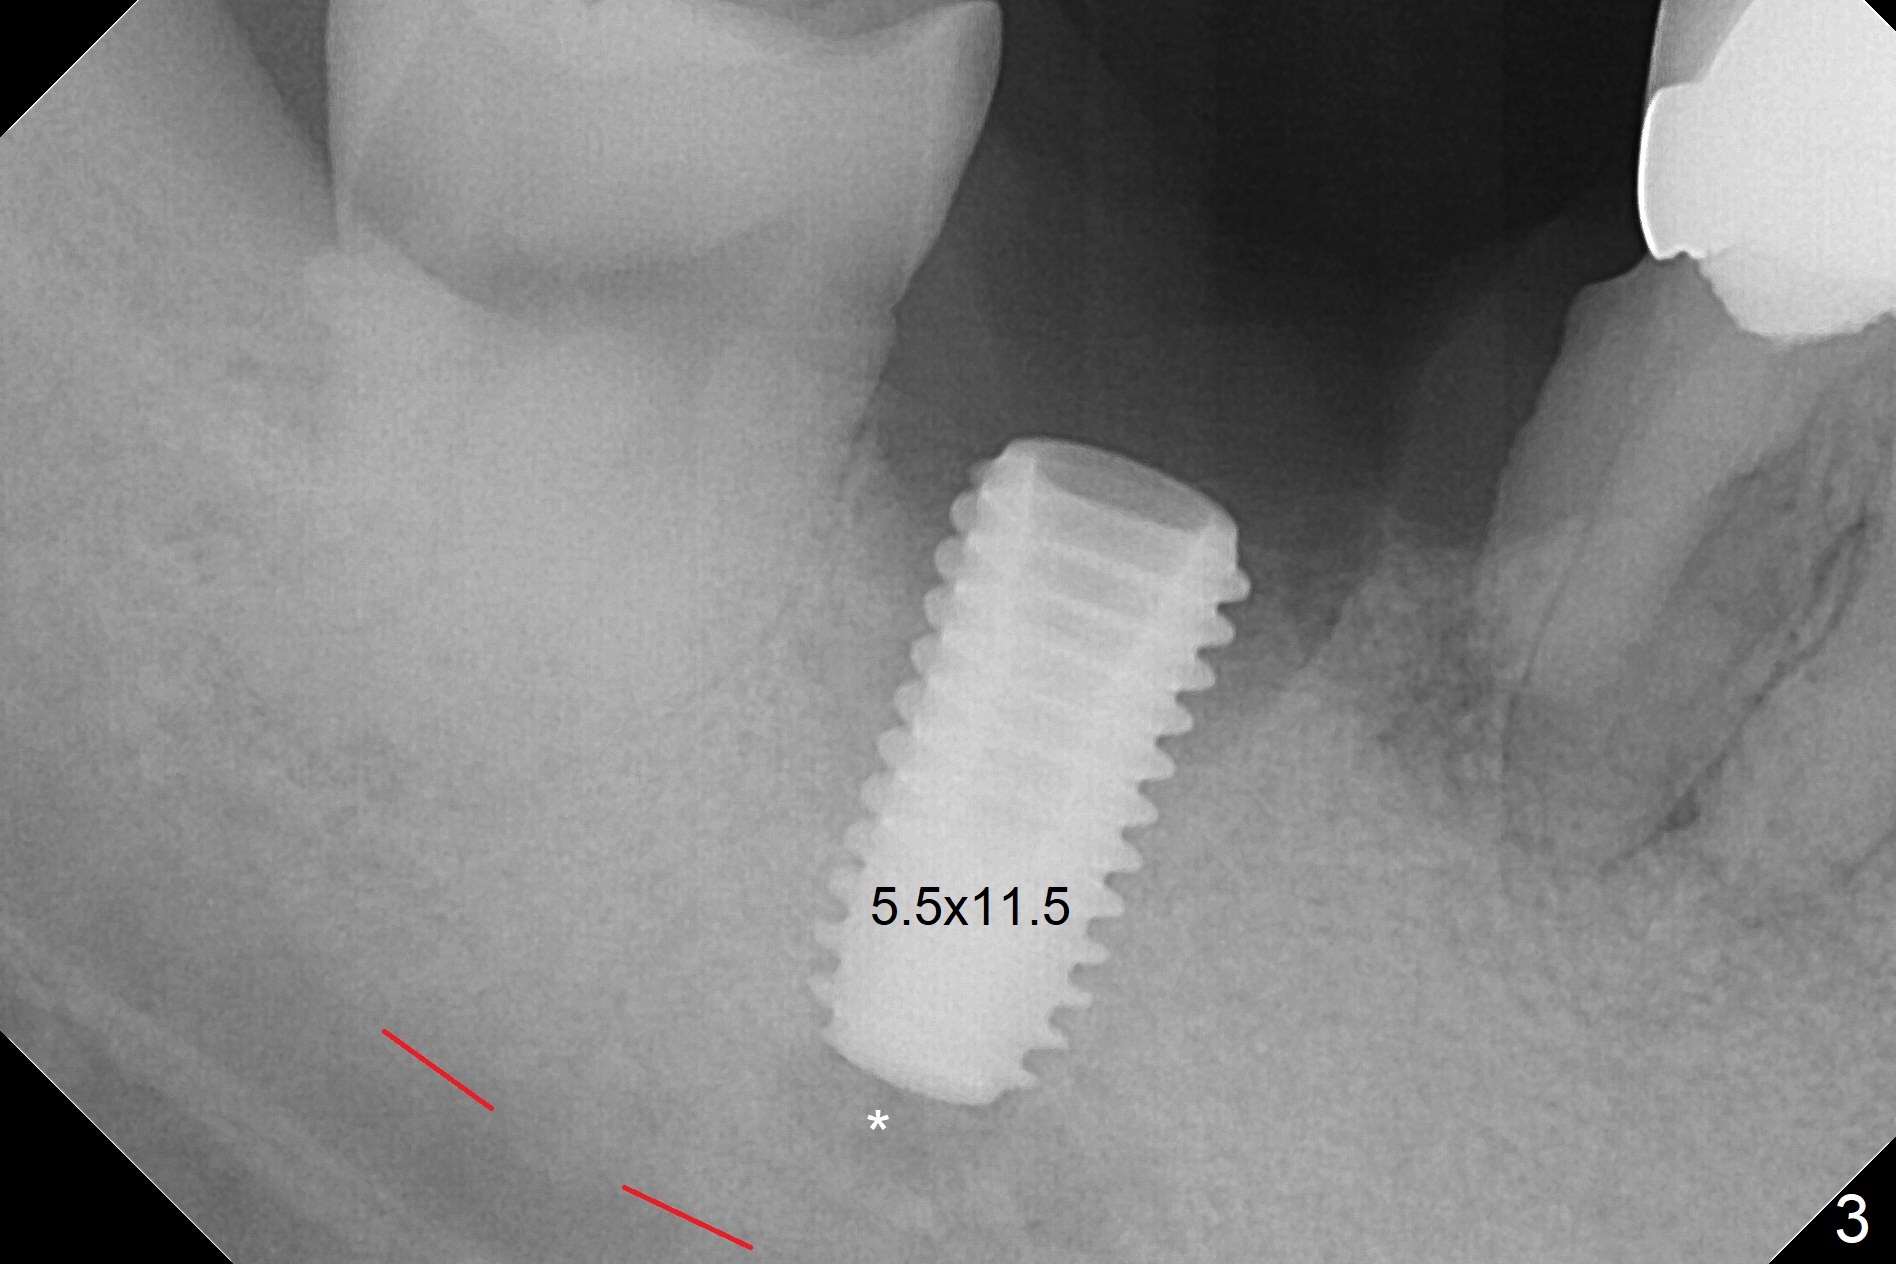

Although the tooth #30 has distobuccal root exposure (Fig.1 <), it is asymptomatic. In contrast the tooth #31 with the distoocclusal caries (*) is symptomatic. After use of 2 mm drill for 18 mm (lingual gingival margin), a calculated parallel pin is inserted (Fig.2 (D: 2 distal roots of the tooth #30)). It appears that a 11.5 mm long implant is appropriate for the site; a 5 mm cuff is expected. Following 4.8 mm drill, a 5.5x11.5 mm implant is placed initially (Fig.3) with an apical space (*) and clearance from the Inferior Alveolar Canal (red dashed line). The implant is placed deeper with placement of a 6.5x4(5) mm abutment and bone graft (*, Fig.4,5). After placement of collagen membrane over the graft, an immediate provisional is fabricated (Fig.6 P) with clearance from the opposing tooth (Fig.7 *). There is no bone loss 3.5 months postop (Fig.8). In fact the abutment has not been seated completely since its placement (Fig.4,5,8). The crown/abutment dislodges 3 years 3 months post cementation (Fig.9). The latter occurs for long incubation time because of opposing partial denture (Fig.10). After trimming proximal surfaces (Fig.11: arrowheads), the abutment remains incompletely seated (Fig.11) due to possible crestal bone interference (Fig.11 *). The smaller abutment by itself remains unseated (Fgi.12). One size small one is completely seated (Fig.13). Impression is taken. Two weeks later the abutment margin is supragingival. After screw torque at 20 Ncm, the crown is cemented with access hole. Excess cement is removed.